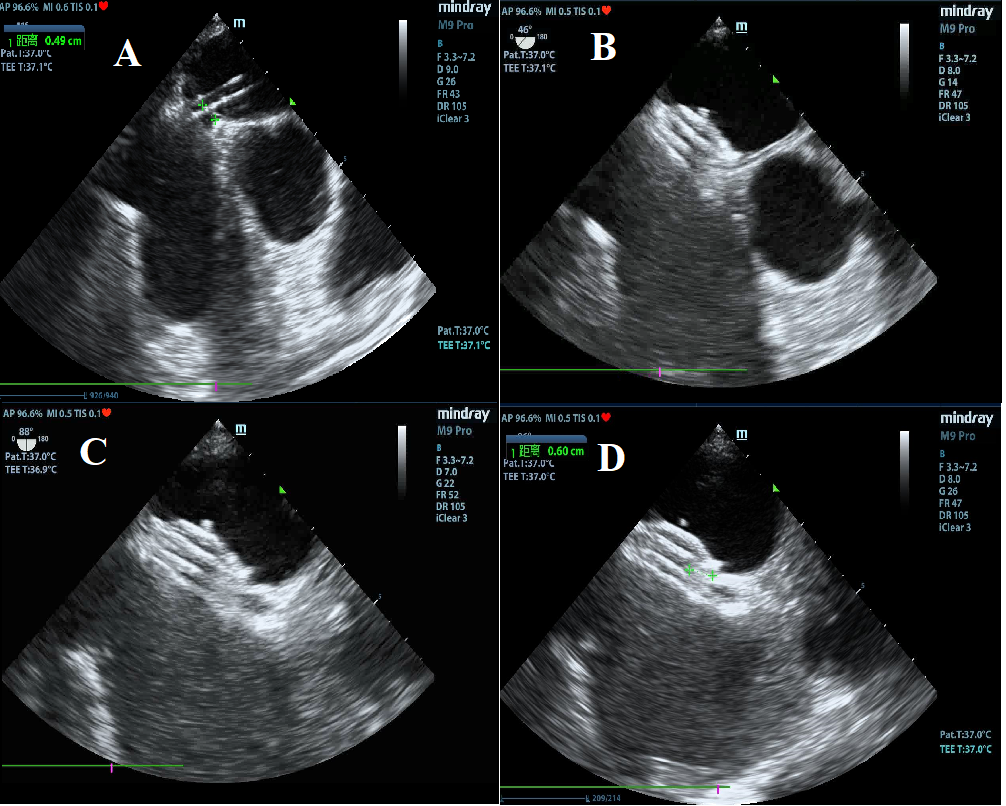

A 48-year-old man was admitted to our hospital with typical symptoms of TIA. Preoperative transesophageal echocardiography demonstrated PFO (Figure 1) and secondary septal pouch on the right (Figure 2, Video 1). Contrast transthoracic echocardiography (TEE) showed a moderate right-to-left shunt (Video 2). To close the secondary septal pouch and the PFO at the same time, successful atrial septal puncture was confirmed under the guidance of TEE (Figure 3A). Subsequently, a 25/25-mm Cera ASD occluder (LifeTech Scientific) was implanted (Figure 4). Post-implantation, the occluder was stable at the implant location (Figure 3B-D). Furthermore, the right-to-left shunt disappeared immediately (Video 3). Thus, ASD occluder implantation may be an effective simultaneous treatment of PFO and secondary septal pouch.

Figure 3. Intraprocedural TEE: (A) atrial septal puncture under the guidance of TEE; stable position of the occluder at (B) 45 and (C) 90 degrees; (D) about 0.6 cm length of the secondary atrial septal was captured within the occluder. ** = length of the distance; TEE = transthoracic echocardiography.